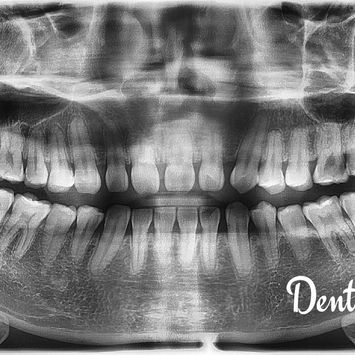

CBCT imaging was taken to evaluate the position of the tooth and its relationship to the inferior dental nerve.

CBCT was taken for surgical planning and evaluation of proximity to the inferior dental nerve.

Post-operative CBCT confirmed complete removal with no remaining tooth fragments.

Post-operative imaging confirmed no residual tooth fragments. The inferior dental nerve remained intact and was not involved in the surgery.